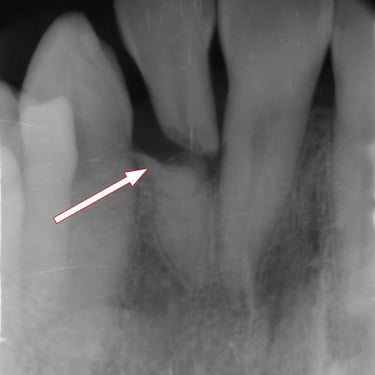

Fractura Radicular Vertical

Una fractura radicular vertical es una fisura que se extiende a lo largo de la raíz del diente, a menudo causada por un trauma o una presión excesiva.

Los pacientes suelen sentir dolor al morder y pueden notar hinchazón.

La fractura generalmente requiere la extracción del diente, ya que es difícil de reparar. Es crucial tratarla rápidamente para evitar infecciones.